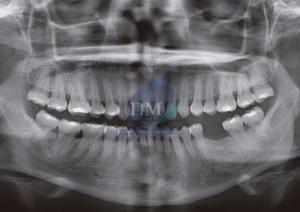

Paciente femenino de 43 años acude al Instituto de Diagnóstico Maxilofacial (sede Miraflores) para evaluación generalizada. A la evaluación de la radiografía panorámica se evidencia un